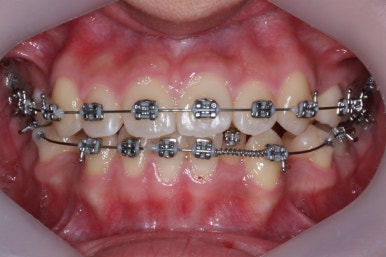

이제 치료가 끝났습니다.

매우 치아가 가지런해졌고, 당연히 덧니는 해소가 되었으며 맞물림도 굉장히 좋아졌습니다.

다른 분드로가의 차이점은 치료 종료 후 유지장치를 할 때 앞니만 하는 것이 아니라 발치한 자리가 다시 벌어지지 말라고 약간 연장해서 유지장치를 부착해 주게 됩니다.

전후과정을 비교해 보겠습니다.

치아가 매우 가지런해졌고, 덧니도 개선이 되었습니다.

맞물림도 굉장히 좋아졌네요.